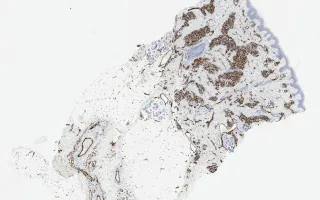

Blood vessels, tufted hemangioma, CD31 stain

Tufted hemangioma

13 month old male infant with a tumour on the shoulder.

Tufted angiomas are benign vascular lesions which often occur on the neck or shoulders of children or young adults. Microscopically, they are comprised of nodules of tightly packed capillaries which may involve the dermis and superficial subcutis. Crescentic cleft-like vessels or semilunar lymphatic channels are generally seen at the periphery of some of the capillary tufts (nodules). These vessels are lined by unremarkable endothelial cells (CD31 positive) and surrounded by pericytes (smooth muscle actin positive). D2-40, a marker of lymphatic endothelial cells, is expressed in the crescentic cleft like vessels, but the proliferative capillaries are negative. The capillary lumina are not readily evident in many areas. GLUT-1 was negative in this case; it is positive in juvenile hemangiomas.

This slide shows CD31 stain, see Related Content for H&E, D2-40, and SMA stains.